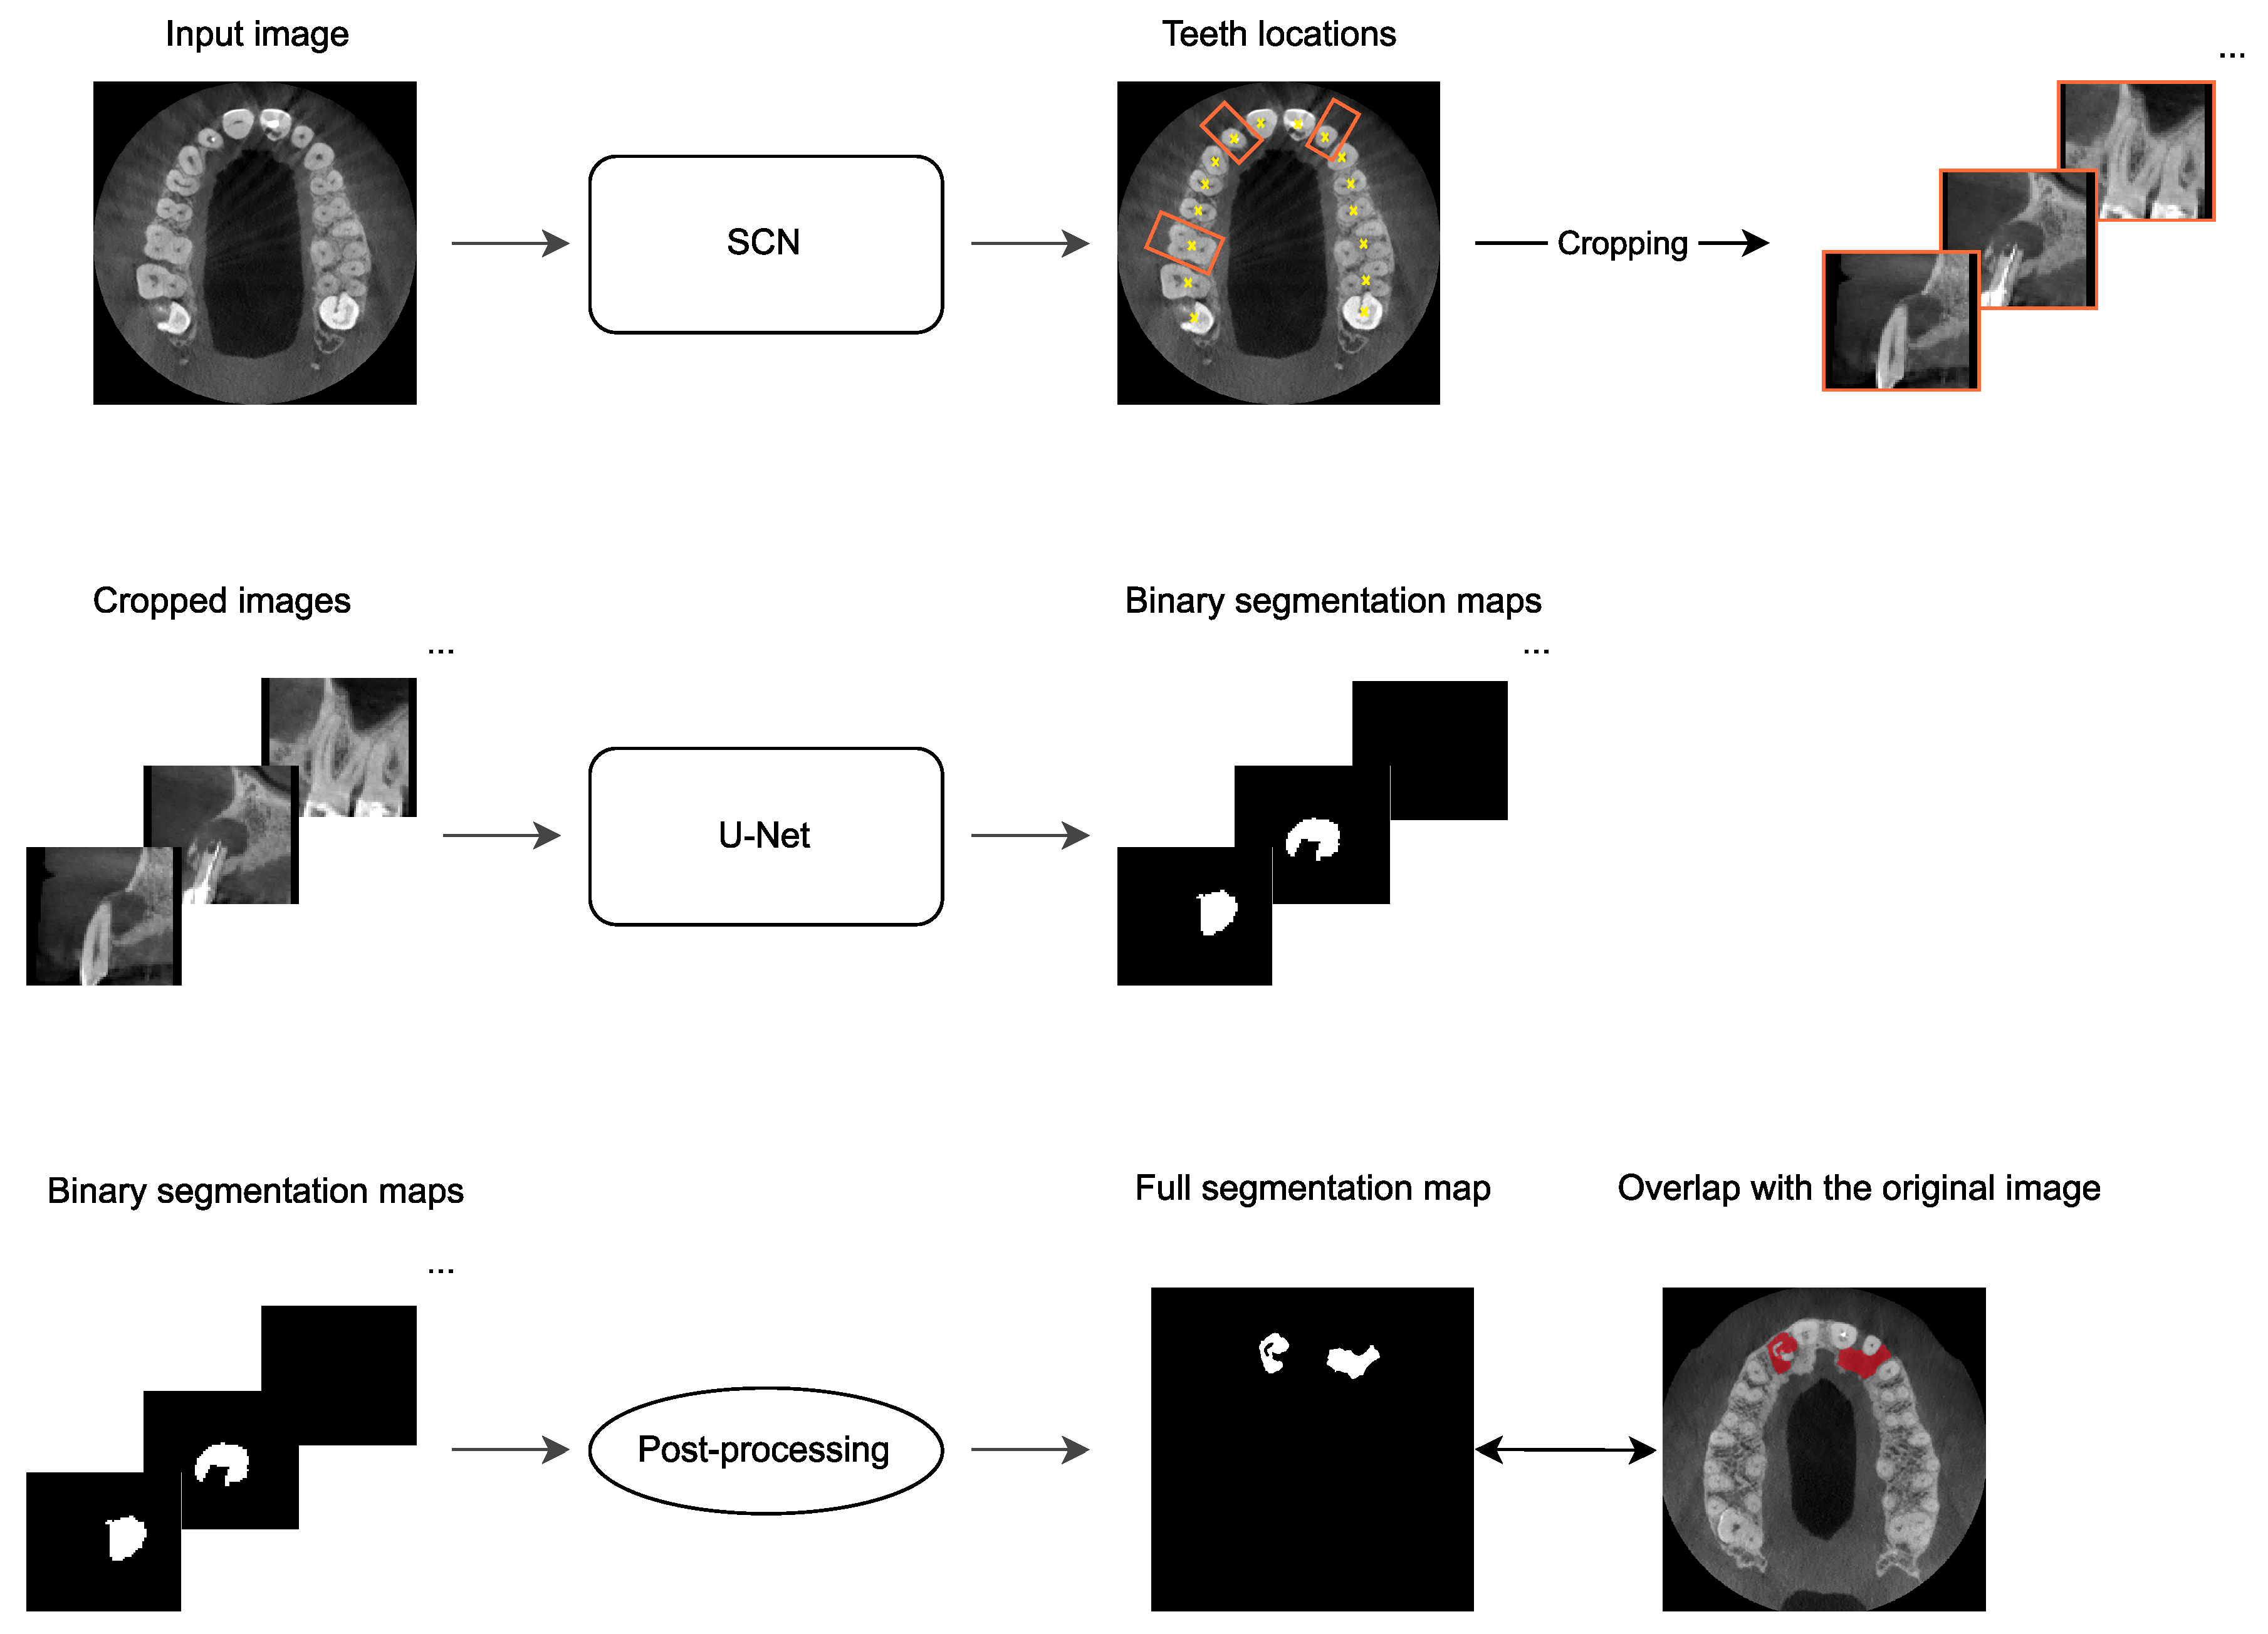

2.4. Automatic PAL Detection

- Hadzic, A.; Kirnbauer, B.; Štern, D.; Urschler, M. Teeth Localization and Lesion Segmentation in CBCT Images using SpatialConfiguration-Net and U-Net. arXiv 2023, arXiv:2312.12189. [Google Scholar] [CrossRef]